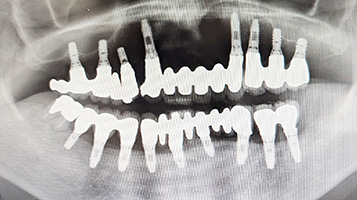

それから32年、現在も1mmの骨吸収もなく、何の問題もなく安定して今日まで機能し続けており当院にとって歴史的な症例となりました。チタンインプラントの信頼性が証明されました。

32年経過症例 / 91歳(2025年現在)・女性

1993年 下顎インプラント埋入時(59歳)

30年経過症例 / 92歳(2025年現在)・男性

1995年 上顎インプラント埋入時(61歳)

2002年 下顎インプラント埋入時(69歳)